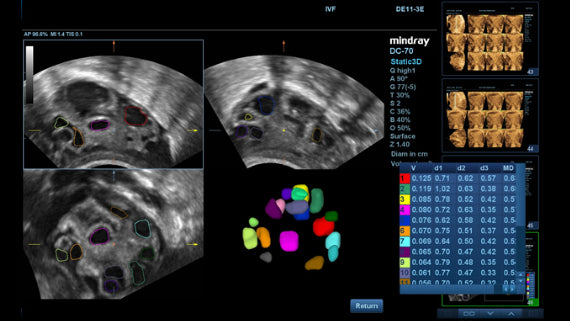

El Ultrasonido premiumDC-70 X-Insight de Mindray es un equipo de última tecnología para ecografías. Ofrece excelente resolución y sensibilidad para una visualización clara y precisa de los tejidos bajo examen. Esta máquina de alto rendimiento ofrece eficiencia y fiabilidad para una mayor precisión diagnóstica.